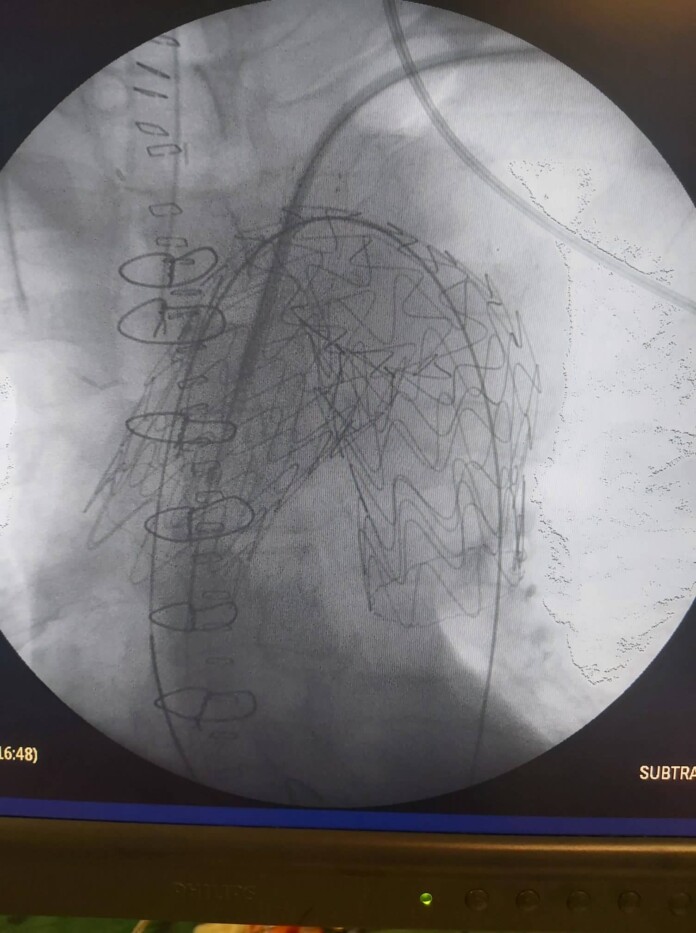

Μία νέα πρωτοποριακή μέθοδος υβριδικής χειρουργικής αντιμετώπισης των διαχωριστικών ανευρυσμάτων του αορτικού τόξου

Στο Πανεπιστημιακό Γενικό Νοσοκομείο Ιωαννίνων άρχισε να εφαρμόζεται πλέον η νέα πρωτοποριακή μέθοδος της υβριδικής χειρουργικής αντιμετώπισης των διαχωριστικών ανευρυσμάτων του αορτικού τόξου, τα οποία είναι πολύ επικίνδυνα για τη ζωή των ασθενών.

Η υπεροχή του νέου τρόπου χειρουργικής αντιμετώπισης αυτής της επικίνδυνης κατάστασης, που πραγματοποιείται σε δύο στάδια, οφείλεται στο γεγονός ότι, πραγματοποιείται χωρίς τη χρήση εξωσωματικής κυκλοφορίας με υποθερμία και χωρίς διακοπή της καρδιακής και εγκεφαλικής λειτουργίας, με αποτέλεσμα οι ασθενείς να αναρρώνουν γρήγορα και με ελάχιστες πιθανότητες επιπλοκών εμφράγματος, εγκεφαλικού, παραπληγίας, αιμορραγίας, λοιμώξεων και θανάτου.